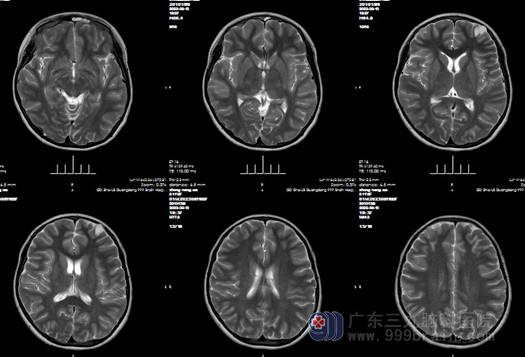

入院后找到了我科的欧阳辉教授,欧阳辉教授和其主治医生看了该患儿的检查片子,为其父母解释道:她的左侧额叶有范围约17×19mm的结节占位病变,考虑低级别神经上皮肿瘤的可能,有明确的手术指征。外十科医生于8月15号为该患儿进行“左侧额叶占位病变切除术”,手术很顺利,病理报告:符合胚胎发育不良性神经上皮肿瘤(DNT)。现在患儿恢复良好,已经出院。

术前影像